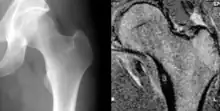

![]() | |

| Osteoid osteoma of the lesser trochanter: X-ray and MRI with marked sclerosis around the nidus | |